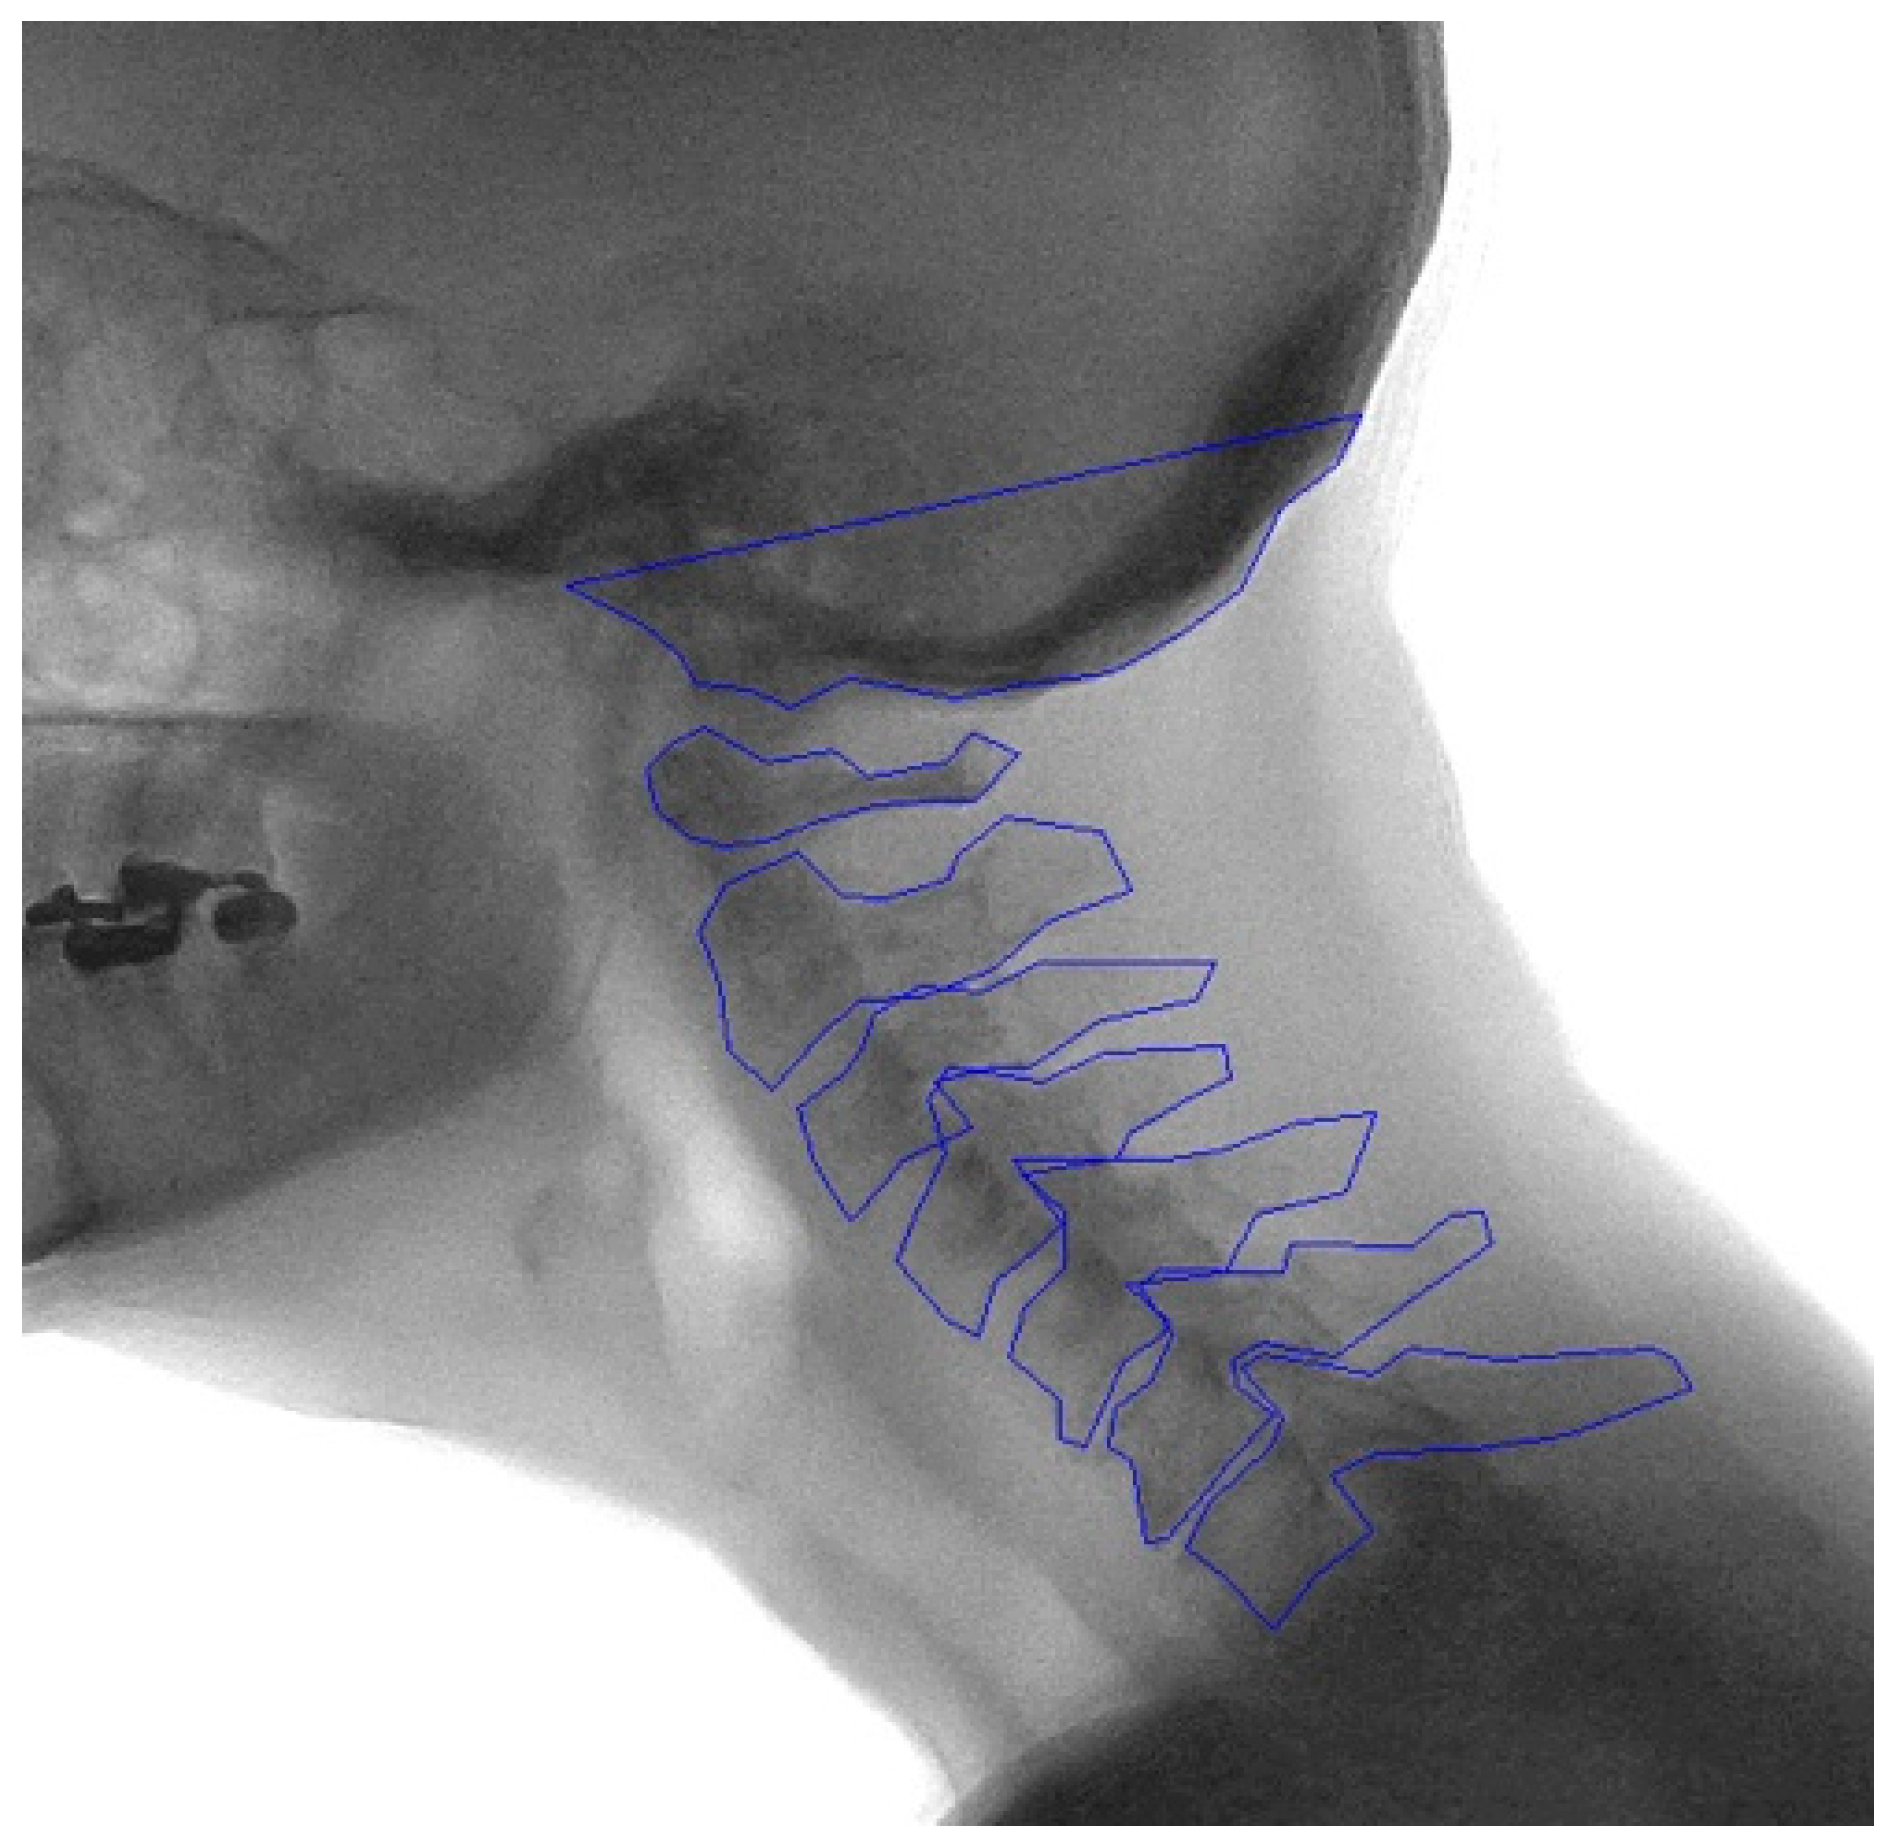

2.2. Manual Annotation

2.3. Development of the Model